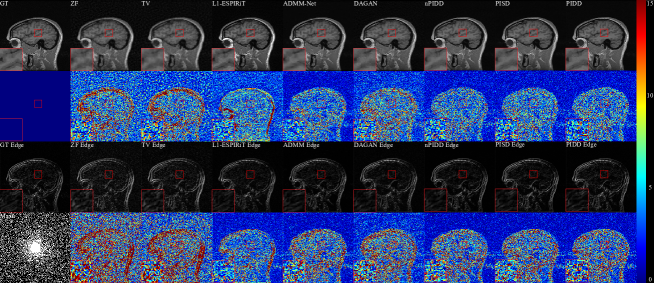

Testing examples of different methods are shown in Fig. 5. Our method is superior to other methods in terms of overall reconstruction quality and edge information reconstruction. We can see that ZF is quite blurred, mixed with many artefacts. Compared with traditional TV and L1-ESPIRiT methods, the noise reduction of ADMM and DAGAN are greatly improved, but the detailed information is still lost significantly. The reconstruction result of L1-ESPIRiT shows rich details, but it is poor in de-noising and time-consuming. Compared with PIDD and PISD, nPIDD lacks multi-channel information. Although the basic structure can be completely restored, and most noise is reduced, the excessive smoothing phenomenon is severe compared to PIDD and PISD. From the zoom-in area, it can be seen that PIDD clearly reconstructs the edge information of the brain, but this structure is very shallow in the results of PISD.

Horizontal line profiles of the samples in Fig. 5 are shown in Fig. 6. ZF and DAGAN still contain lots of noise, while our proposed methods preserve more detail information. Zoom-in areas clearly show that the line profile of PIDD-GAN achieve more accurate than other methods.